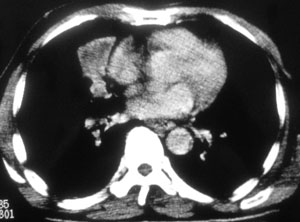

性别 男  62岁 因咳嗽及左肱骨剧烈痛疼数天来院检查。

右中央型肺癌并肱骨转移。

考虑右肺中叶肺癌并左肱骨转移伴病理性骨折。

支持右肺中心型肺癌并肺内及左肱骨转移伴病理性骨折

右肺中心型肺癌并中叶不张,左肱骨溶骨性转移并病理骨折。